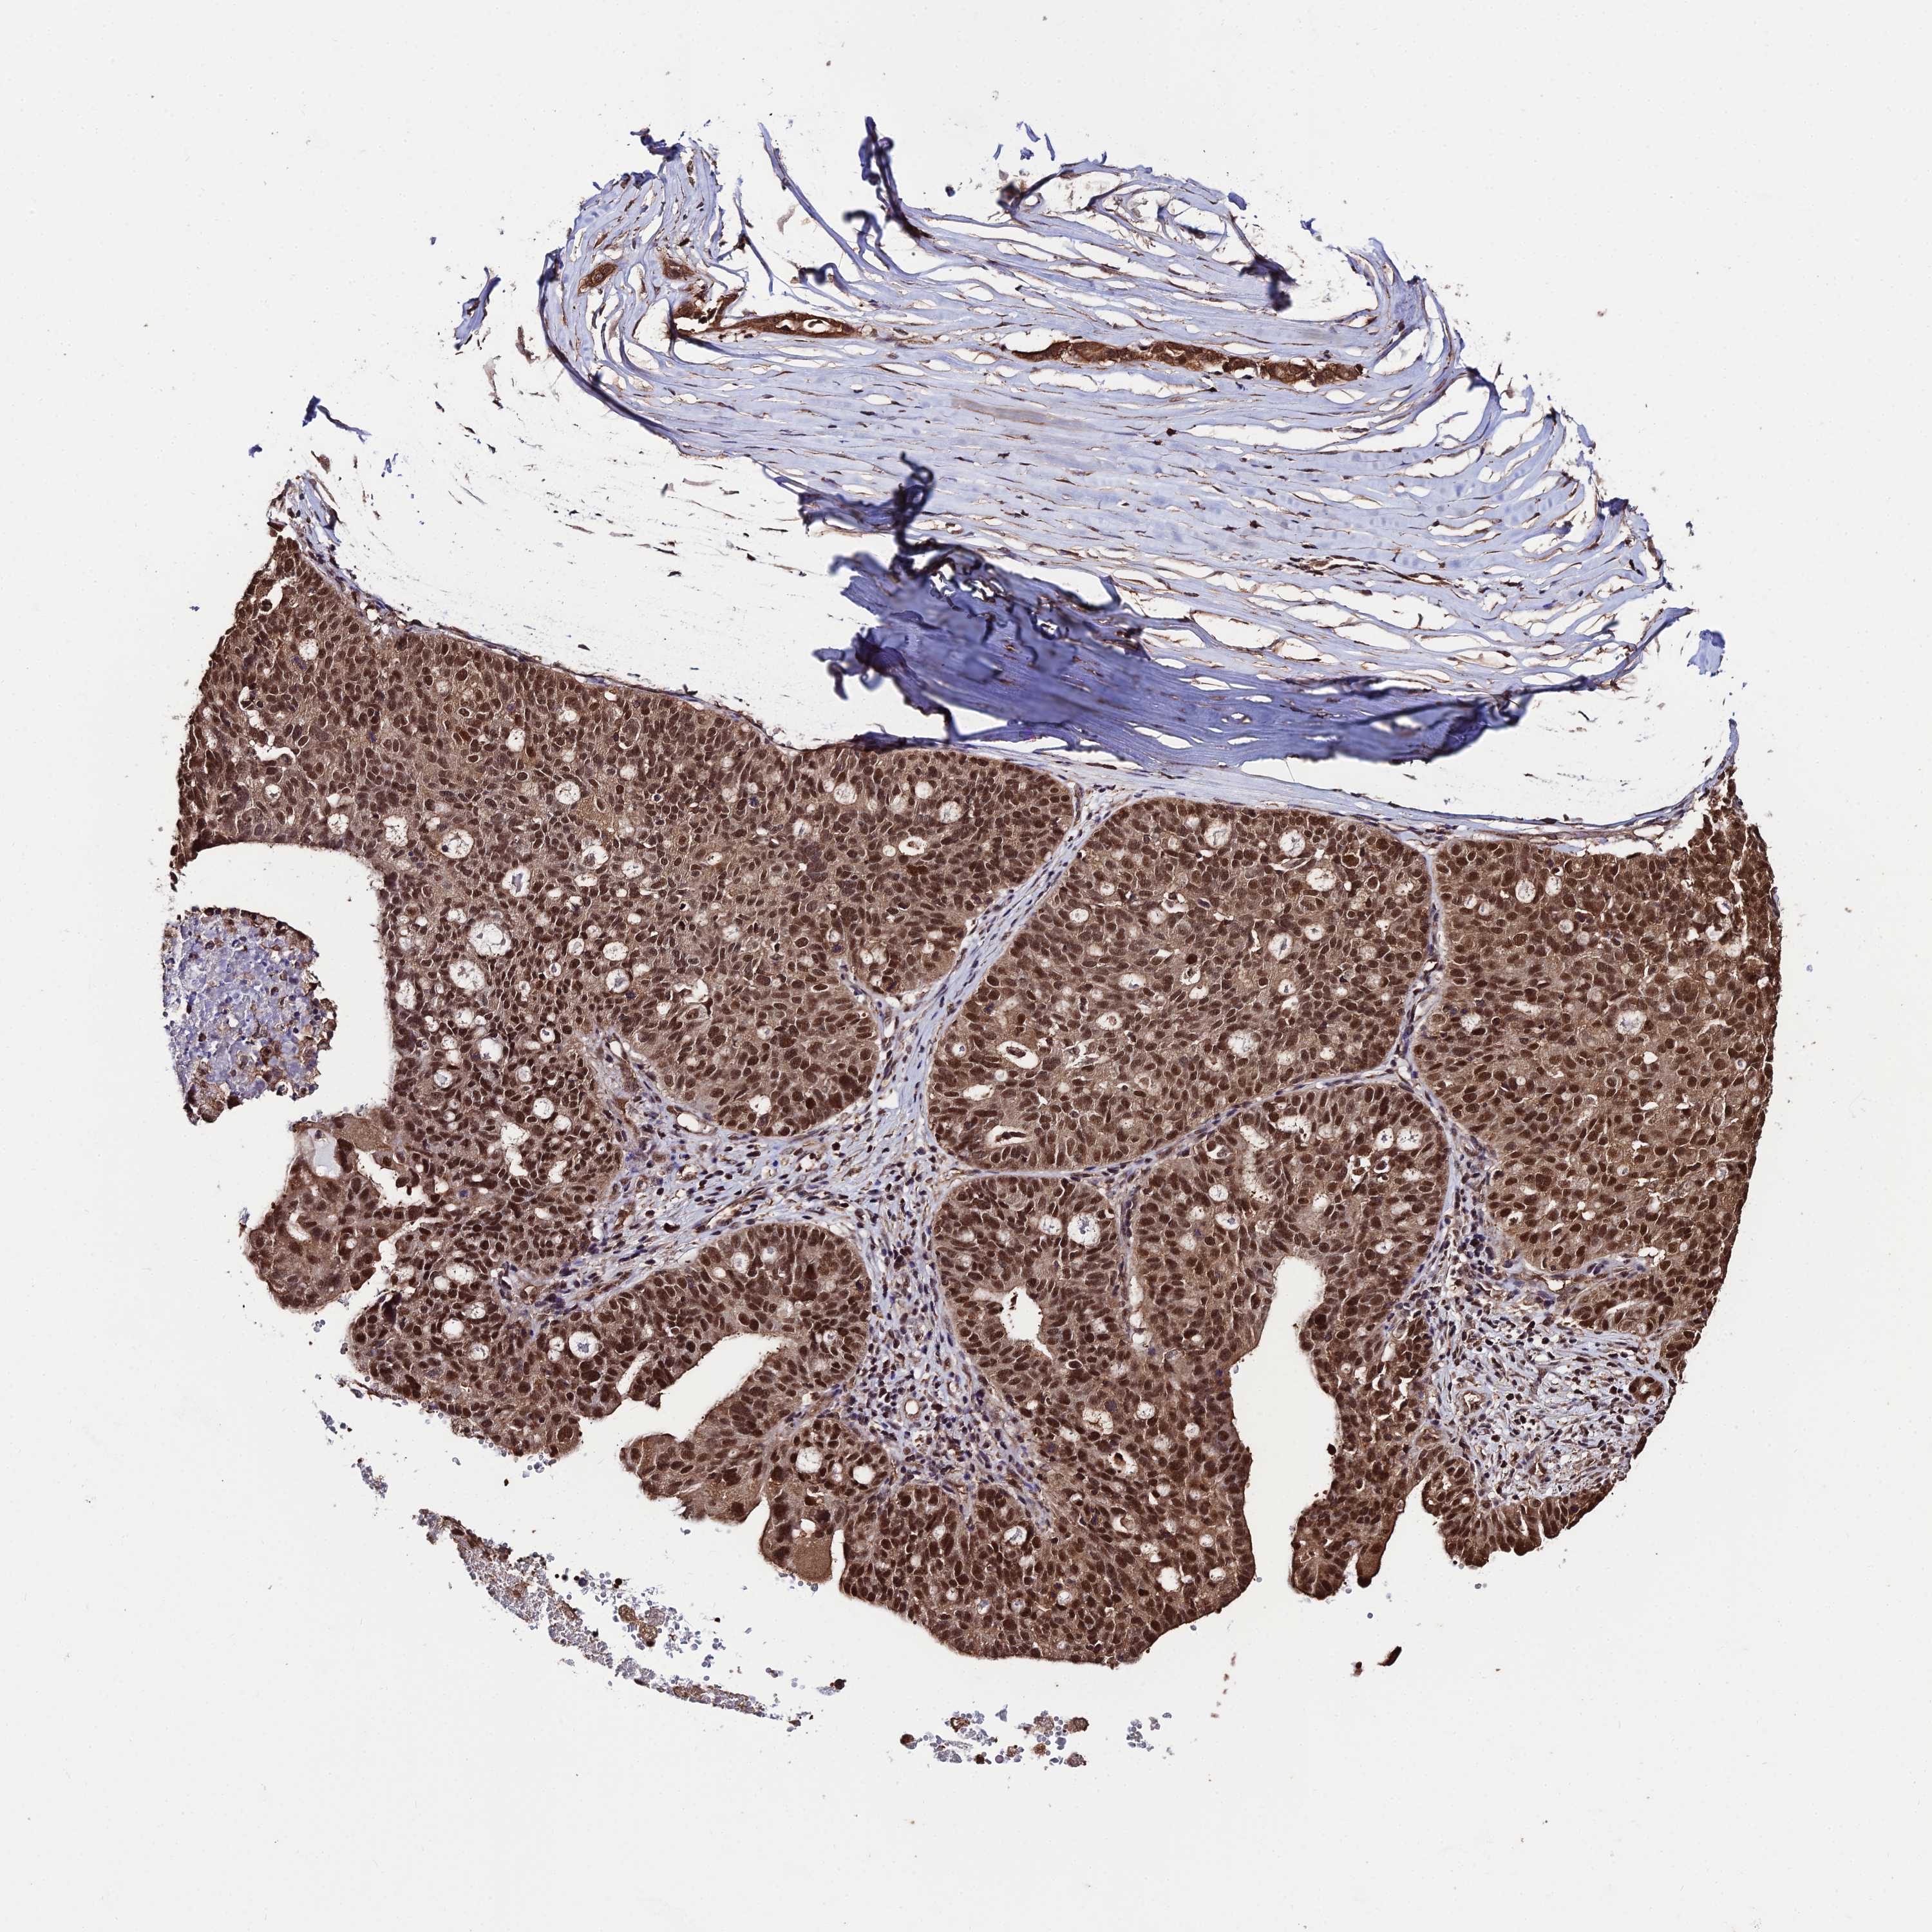

OVARIAN CANCER - Protein expressioni

A mouse-over function shows sample information and annotation data. Click on an image to view it in a full screen mode. Samples can be filtered based on level of antibody staining by selecting one or several of the following categories: high, medium, low and not detected. The assay and annotation is described here.

Note that samples used for immunohistochemistry by the Human Protein Atlas do not correspond to samples in the TCGA dataset.

Antibody stainingi

Antibody staining in the annotated cell types in the current human tissue is reported as not detected, low, medium, or high, based on conventional immunohistochemistry profiling in selected tissues. This score is based on the combination of the staining intensity and fraction of stained cells.

Each image is clickable and will lead to virtual microscopy that enables deeper exploration of all samples and also displays staining intensity scores, fraction scores and subcellular localization as well as patient and tissue information for each sample.

Antibody HPA043837

Staining

High

Medium

Low

Not detected

Intensity

Strong

Moderate

Weak

Negative

Quantity

>75%

75%-25%

<25%

None

Location

Nuclear

Cytoplasmic/membranous

Cytoplasmic/membranous,nuclear

Cystadenocarcinoma, serous, NOS

Carcinoma, endometroid

Cystadenocarcinoma, mucinous, NOS

Carcinoma, NOS